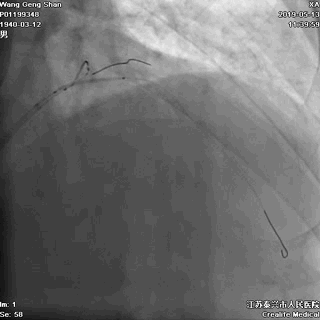

01 导丝进前三叉分支

02 处理LAD中段病变

对角支导丝到位

左冠共计5根导丝